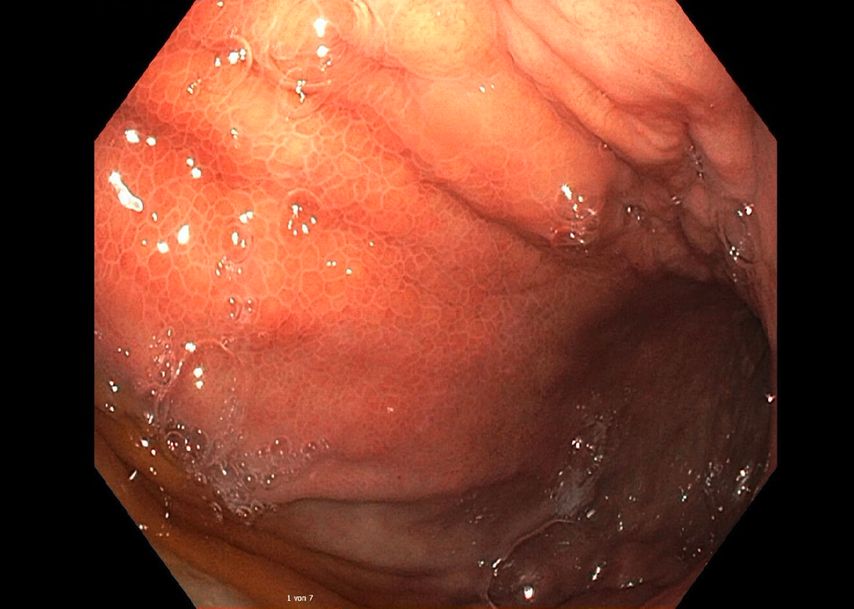

Eine Gastroskopie unter Intubationsnarkose wird angeschlossen (Abb.2). Gastroskopisch ist der Magen leer, die Schleimhaut adäquat durchblutet, ohne Ulzerationen oder malignomsuspekte Areale. Die einzige Auffälligkeit: Der Magen entfaltet sich nicht gänzlich, und zwar aufgrund einer submukös liegenden, verdrängenden Raumforderung im Bereich der Magenvorderwand. Aufgrund der Raumforderung kann der Pylorus nicht eingesehen werden.